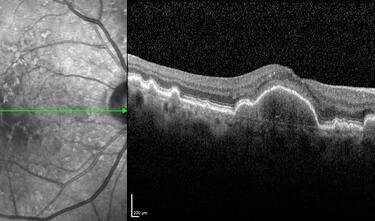

Clase 15 - Depósitos y signos específicos en DMAE no neovascular

Clase 16 - Distrofia hereditarias de la retina que simulan DMAE no neovascular

Clase 18 - Signos estructurales diferenciales entre neurodegeneración y exudación en DMAE